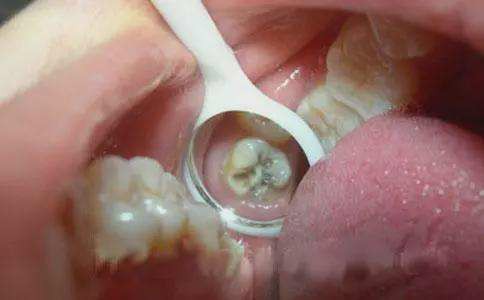

宝宝从6个月开始长牙,2岁半完成乳牙列的发育,到6岁开始乳牙才依次松动,直到12岁左右完成乳牙的替换。很多儿童龋齿从早期的牙齿发黑、残缺到后来的缺失,继而影响恒牙的生长,跟父母的重视程度息息相关。当孩子刚开始呈现牙疼、牙齿发黑状态时,一定要及时就医,避免小问题酿成大祸!

很多父母对儿童乳牙的保护意识相当薄弱,想着孩子的牙齿12岁左右就会被替换掉,就采取放养的态度对待龋齿的发生。殊不知,龋齿会导致蛀牙根尖化脓,产生炎症。济南全好口腔王医生提醒家长:龋齿对于儿童的危害远大于承认,这种危害既影响局部也影响全身,尤其是乳牙龋齿及继发病变造成的后果,比恒牙龋齿更难。